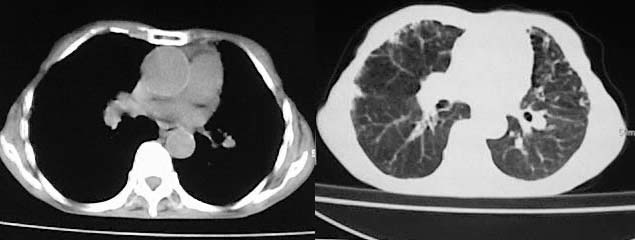

以下是引用有风的日子在2008-5-2 12:13:00的发言:[br][emb10][br][br]肺ca?有病理支持吗?[br][br]我看更象是肺tb并支扩、间质性肺炎。最好拿个病理结果来,不然这点影像资料诊断肺ca是难以服人的![br][br]至于主动脉瘤的诊断问题,国外认为≥4.0cm就可诊断了,国内对此诊断标准更为严格。患者升主动脉明显增粗,即>4cm。你诊断个升主动脉扩张并不为过!